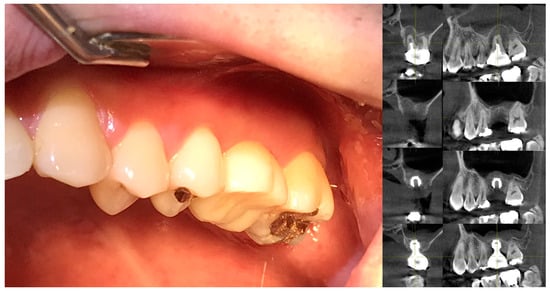

Figure 4 showcases a successful case of SPIs, demonstrating stable and esthetic outcomes. The clinical photos highlight natural soft tissue integration, while the CBCT images provide peri-implant soft tissue analysis, including measurements of transitional zone length (TZL) and soft tissue thickness (STT). These parameters help to evaluate the relationship between structural support and biological stability achieved with SPIs.

Figure 4.

Clinical and radiographic outcomes of an SPI-restored upper left first molar. Upper Two Images (Clinical Photos): Show the restored upper left first molar with well-integrated soft tissue, demonstrating a natural emergence profile and coronal flaring of the implant restoration. These features contribute to both biological stability and esthetic success. Lower Left Image (CBCT Cross-Section, Buccolingual View): Displays the implant placement. While the PCO effect suggests that the buccal margin is positioned more apically than the mesiodistal margin—resulting in a shorter overall distance from the fixture–abutment connection (FAC) to the soft tissue margin in the buccal aspect—this does not necessarily imply that the crestal zenith at the buccal side must always be positioned apically. Unlike the palatal side, where the crest may be observed at an epicrestal level, implant placement at the buccal side can still be subcrestal, provided it meets the required vertical depth for peri-implant stability or is intended to enhance the bone phenotype. Lower Right Image (CBCT with Measurements): Highlights the transitional zone length (TZL) and soft tissue thickness (STT), showing the vertical and horizontal dimensions of the peri-implant soft tissue. Additionally, it reflects the influence of the mesiodistal crestal slope (MDCS), emphasizing how ridge morphology affects implant positioning, peri-implant soft tissue stability, and overall emergence profile.